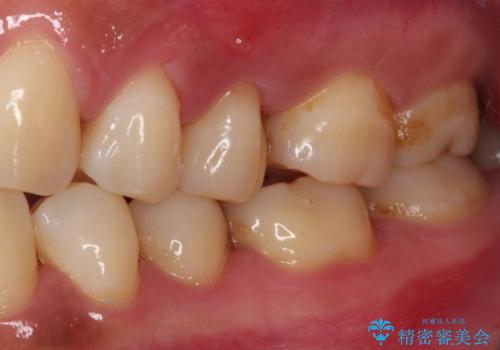

- 上下の歯が接触する度に痛みを感じるとのことで来院された患者様です。

診査の結果、既に歯の神経は失活しており、レントゲンより根尖部に病変を認めました。

根管治療を行った後にオールセラミッククラウンにて補綴することとしました。